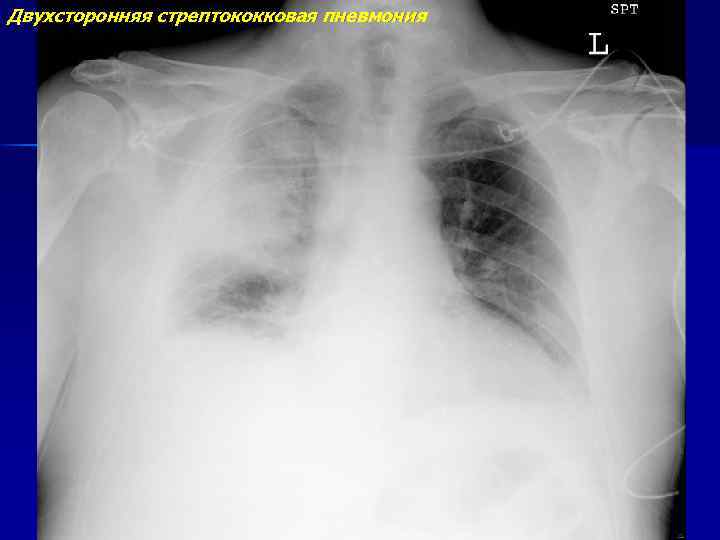

Двухсторонняя стрептококковая пневмония